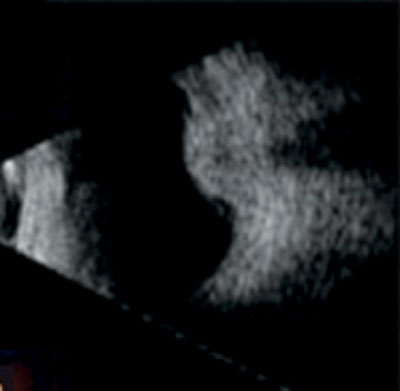

Figure 1: Typical dome-shaped choroidal lesion on B scan ultrasonography [7].

Fundus examination revealed an irregularly shaped, moderately pigmented opacity in the left fundus with disruption of Bruch’s membrane. Following these findings, A and B-scan ultrasonography (US) was performed. B-scan US revealed an irregular peaked choroidal mass 6mm with an exudative retinal detachment inferior to the mass. The lesion demonstrated low to medium reflectivity on A-scan US.